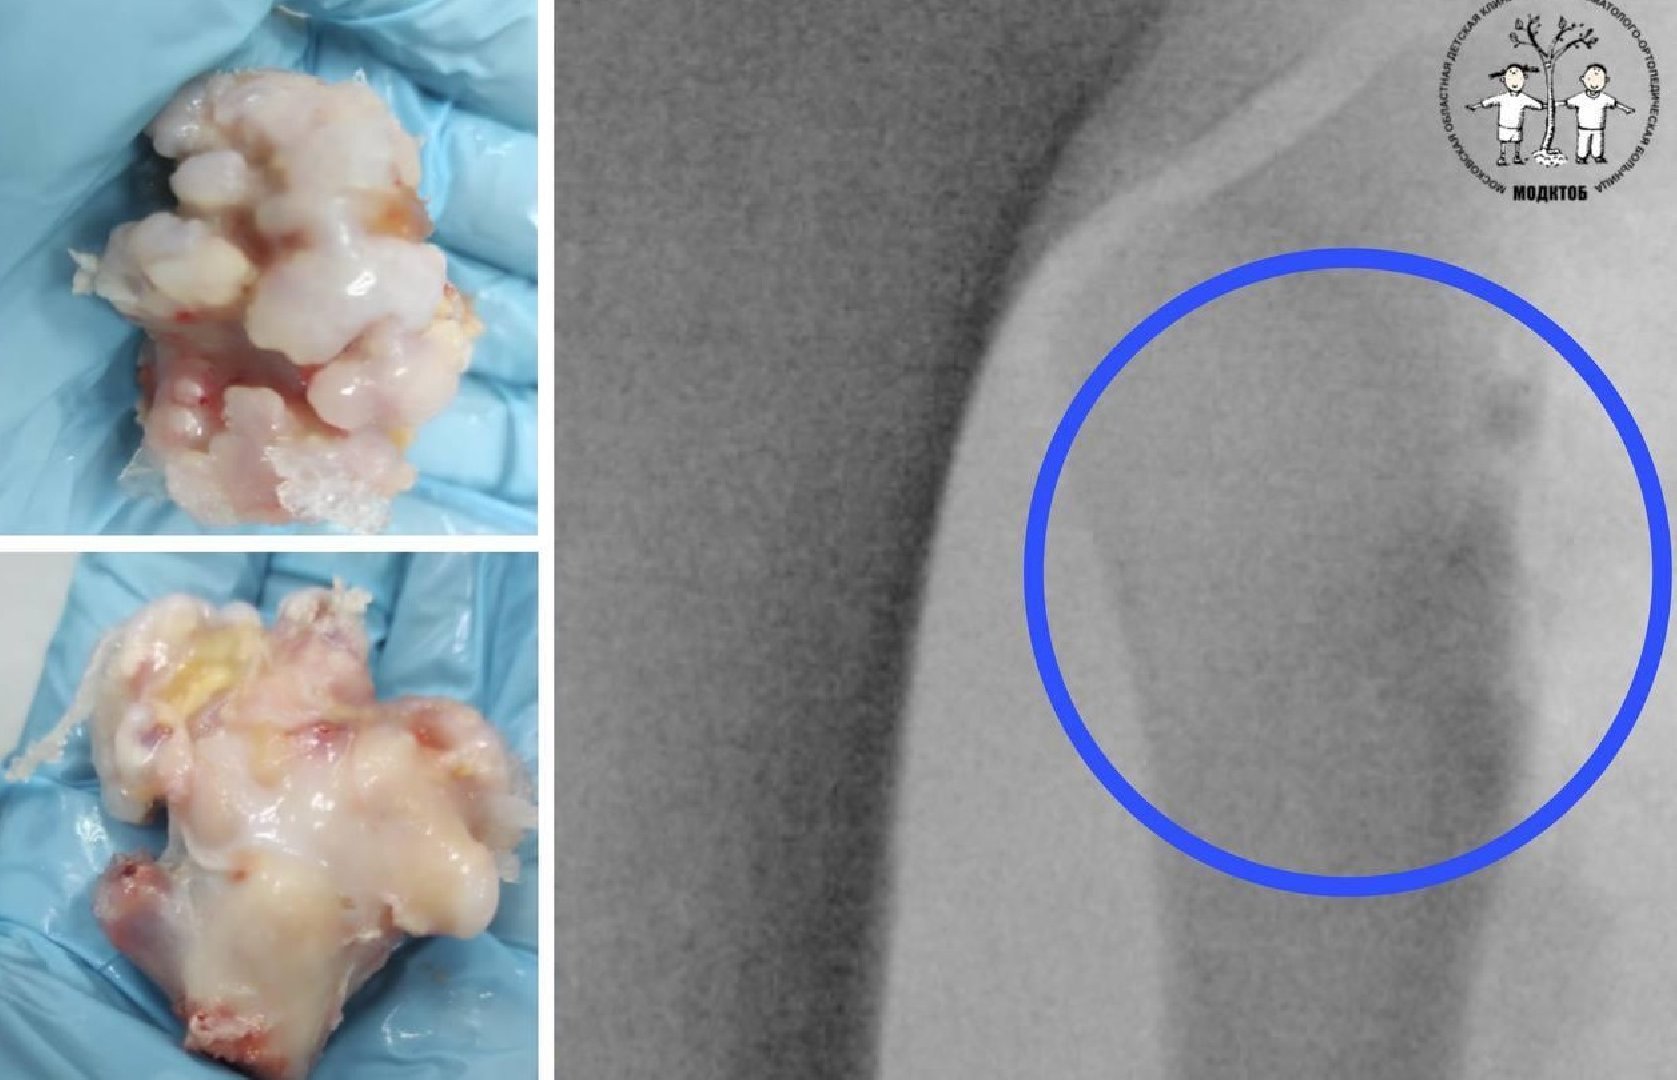

Подросток и его родители обратились в МОДКТОБ, где в ходе обследования травматолог-ортопед диагностировал у пациента остеохондрому. Это доброкачественное новообразование кости. Оно выглядит как нарост на поверхности кости, покрытый хрящевой тканью.

«Неприятность патологии заключается в том, что она не вызывает боли и дискомфорта в начале развития. Однако опухоль может незаметно вырасти до внушительных размеров и привести к деформации костей конечностей, а при самых неудачных локализациях – к закрытию зон роста. У заболевания нет обратного развития, единственный метод лечения – хирургический. Поэтому мы удалили пациенту опухолевидное образование в пределах здоровой костной ткани», – рассказал заведующий отделением №2 МОДКТОБ Сергей Антипин.Сейчас подросток чувствует себя хорошо, его уже выписали на амбулаторное лечение.